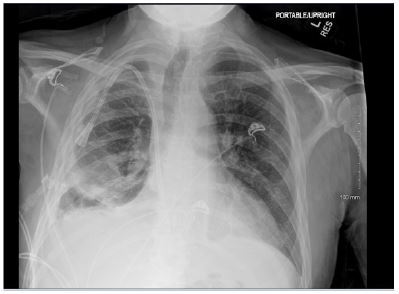

Patient presented with elevated blood pressure at 174/88. BMP was significant for Na 133, K 4.6, BUN 29, Cr 5.3. CMP is significant for Albumin 2.5. CBC was significant for Hb 8.7, Hct 25.0. D-dimer was found elevated at 4,670. PT and INR were normal. ABG significant for pH 7.52, pCO2 31.4, HCO3 25.3. A chest x-ray on admission demonstrated a large right-sided pleural effusion, contributing to significant compressive atelectasis of the right lung and leftward deviation of the mediastinal structures. Thoracentesis was performed, which demonstrated blood- tinged serosanguinous fluid. Transthoracic echocardiogram demonstrated EF 60-65%, LV diastolic dysfunction, with trace mitral and tricuspid regurgitation, and was negative for pericardial effusion. CT Chest demonstrated a large volume right-sided pleural effusion without pneumothorax, with extensive progressive atelectasis throughout the right lung. There was also a trace left-sided pleural effusion and pleural thickening with round atelectasis in the posterior left lower lobe, as well as minimal interstitial edema in the left lung. A chest tube was placed with consistent drainage throughout admission. Repeat chest x-rays continued to demonstrate pleural effusion. Thoracotomy, decortication, and pleurodesis were performed with Video-Assisted Thoracoscopic Surgery (VATS), with significant improvement of symptoms. The pleural fluid biopsy was negative for malignancy and revealed fibrocollagenous tissue with chronic inflammation and a few reactive epithelial cells. Thorough review of the patient’s medication list led to suspicion that the patient’s 50 mg Hydralazine three times a day may be the offending agent. Anti-histone antibody titers were found to be elevated at 3.7. Free Kappa and Lambda light chains were elevated. Antinuclear Antibody (ANA) titers were found to be negative. Hydralazine was discontinued, and after chest tube removal and improved chest x-ray, the patient was discharged home. It was recommended that the patient follow up with their primary care provider and rheumatologist.

Figure 1: Chest radiographs demonstrating large right sided pleural effusion, and small left lower pleural effusion.